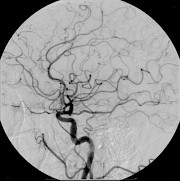

Digitale Substraktions-Angiographie (DSA) ist die neueste Anschaffung im Hause Hüttental. Dieses ungefähr 1 Million Euro teure Gerät soll zum Beispiel die Behandlung von Aneurysmen im Kopf verbessern.

„Die Verbesserung zum alten Gerät liegt darin, dass nun weniger Strahlung und weniger Kontrastmittel benötigt wird“, sagt Dr. Burkhardt Irnich, Chefarzt der Radiologie. Die Radiologie arbeiten seit Ende 2010 mit dem neuen Gerät.

Die DSA Anlage funktioniert in groben Zügen, so wie der Name es schon sagt mit Subtrahierender Technik. Es werden in jeder Serie die erstellt wird, erstmal mindestens 2 native Bilder gemacht die dann voneinander subtrahiert werden. Man hat dann das Nullbild oder Leerbild. Wenn dann das Kontrastmittel (meist Jodhaltig) gespritzt wird, sieht man dann halt nur das Gefäß, da das KM eine neue höhere Dichte mit ins Bild nimmt. Zudem ganzen kann man mit dieser DSA Anlage auch 3D Bilder erstellen. Das System hilft beim Zurechtfinden der nur 3mm starken Kapillargefäße und der direkten Beseitigung der Aneurysmen durch das Team das meist aus 2 Radiologen und 2 MTRA´s besteht. Das schnelle Vorgehen bei Schlaganfallpatienten ist besonders wichtig. In etwa 1300 Schlaganfallpatienten werden jährlich im Kreisklinikum behandelt.

Die DSA Anlage funktioniert in groben Zügen, so wie der Name es schon sagt mit Subtrahierender Technik. Es werden in jeder Serie die erstellt wird, erstmal mindestens 2 native Bilder gemacht die dann voneinander subtrahiert werden. Man hat dann das Nullbild oder Leerbild. Wenn dann das Kontrastmittel (meist Jodhaltig) gespritzt wird, sieht man dann halt nur das Gefäß, da das KM eine neue höhere Dichte mit ins Bild nimmt. Zudem ganzen kann man mit dieser DSA Anlage auch 3D Bilder erstellen. Das System hilft beim Zurechtfinden der nur 3mm starken Kapillargefäße und der direkten Beseitigung der Aneurysmen durch das Team das meist aus 2 Radiologen und 2 MTRA´s besteht. Das schnelle Vorgehen bei Schlaganfallpatienten ist besonders wichtig. In etwa 1300 Schlaganfallpatienten werden jährlich im Kreisklinikum behandelt.